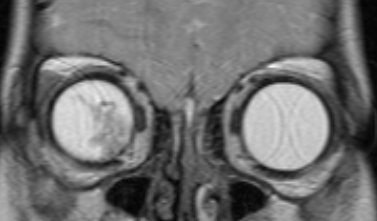

МРТ головного мозга и орбит

Магнитно-резонансная томография дает возможность в деталях увидеть распространение процесса за пределы глазного яблока и точно определить стадию болезни. Такое исследование нужно проводить всем пациентам, у которых ретинобластома диагностирована впервые. Контраст при МРТ повышает информативность.

image004.pngРис. 2. Визуализация ретинобластомы с помощью МРТ. Клиническая группа В

image005.pngРис. 3. Визуализация ретинобластомы с помощью МРТ. Размеры образования соответствуют клинической группе D

image006.pngРис. 4. Визуализация ретинобластомы с помощью МРТ. Фронтальное изображение орбит. Клиническая группа D